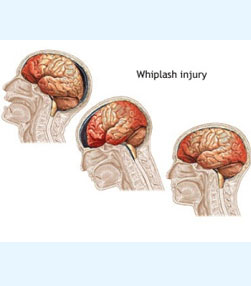

- Head trauma - More than 1500 cases.